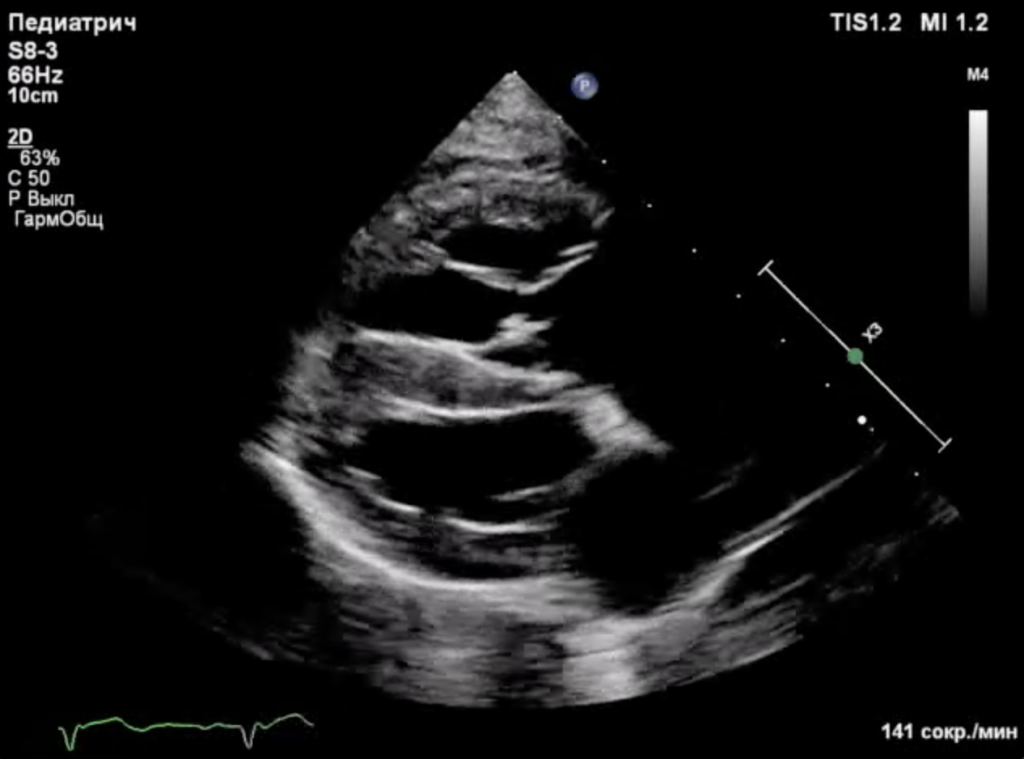

Спустя 8 дней после проведения операции было выполнено контрольное эхокардиографическое исследование, результаты которого выявили следующие изменения (фото 6-8):- Конечный диастолический размер (КДР) правого желудочка снизился с 34 до 22 мм.

- Площадь регургитационного отверстия уменьшилась с 2,7 до 0,7 см2.

- Степень регургитации - moderat/severe.

- Отсутствие застоя в системных венах.

- Систолическая функция ПЖ – в пределах нормы.